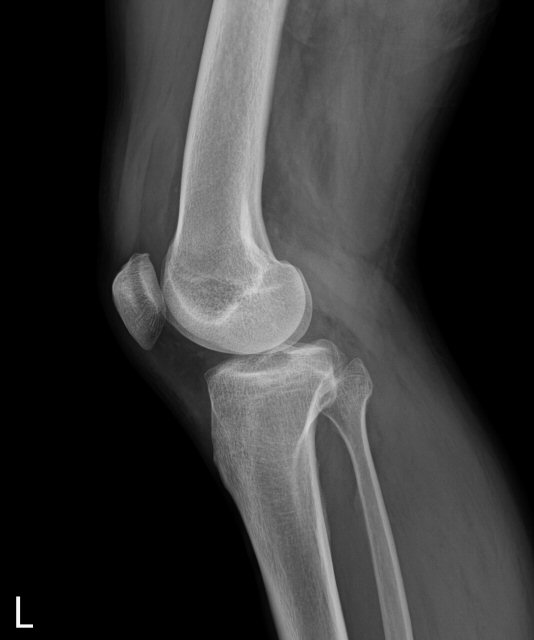

´Ü¼ø¹æ»ç¼±°Ë»ç

ƯÀÌ ¼Ò°ß ¾øÀ½, 1ÁÖ ÈÄ ÃßÀû°Ë»ç »çÁø¿¡¼­ ¹æ»ç¼±°¨¼âÀ½¿µÀ» º¸ÀÓ(»çÁø 6, 7)